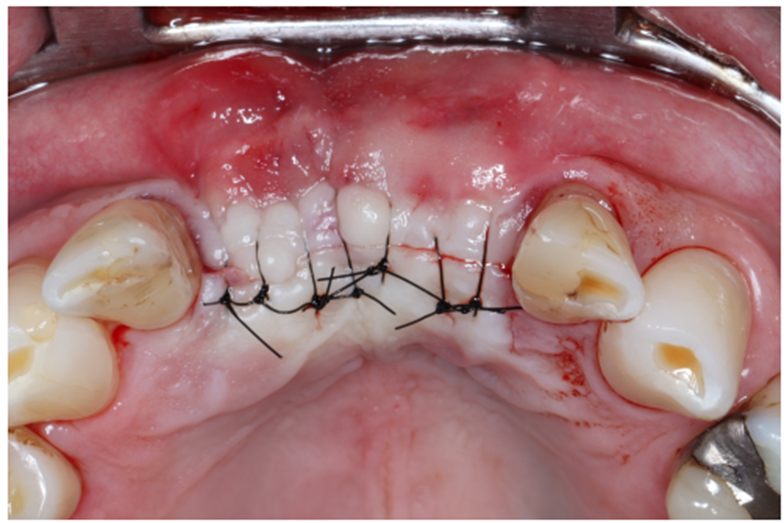

Após oito meses, foi realizada nova tomografia para análise do ganho ósseo vertical, assim como o planejamento dos implantes do tipo Cone Morse Maestro – Implacil De Bortoli (Figura 7). Foram planejados e realizados dois implantes 3.5 X 11 mm Cone Morse Maestro após remoção da membrana Cytoplast, devido ao ótimo ganho ósseo vertical, evidenciando sucesso da técnica de regeneração óssea guiada (Figuras 8, 9 e 10). Após a espera de apenas três meses devido a qualidade do implante e suas câmaras de cicatrização, o que possibilita uma osseointegração precoce, foram realizadas duas metalocerâmicas parafusadas sobre pilares Ideale reto, da Implacil De Bortoli, devido ao ótimo posicionamento tridimensional (Figuras 11 e 12).